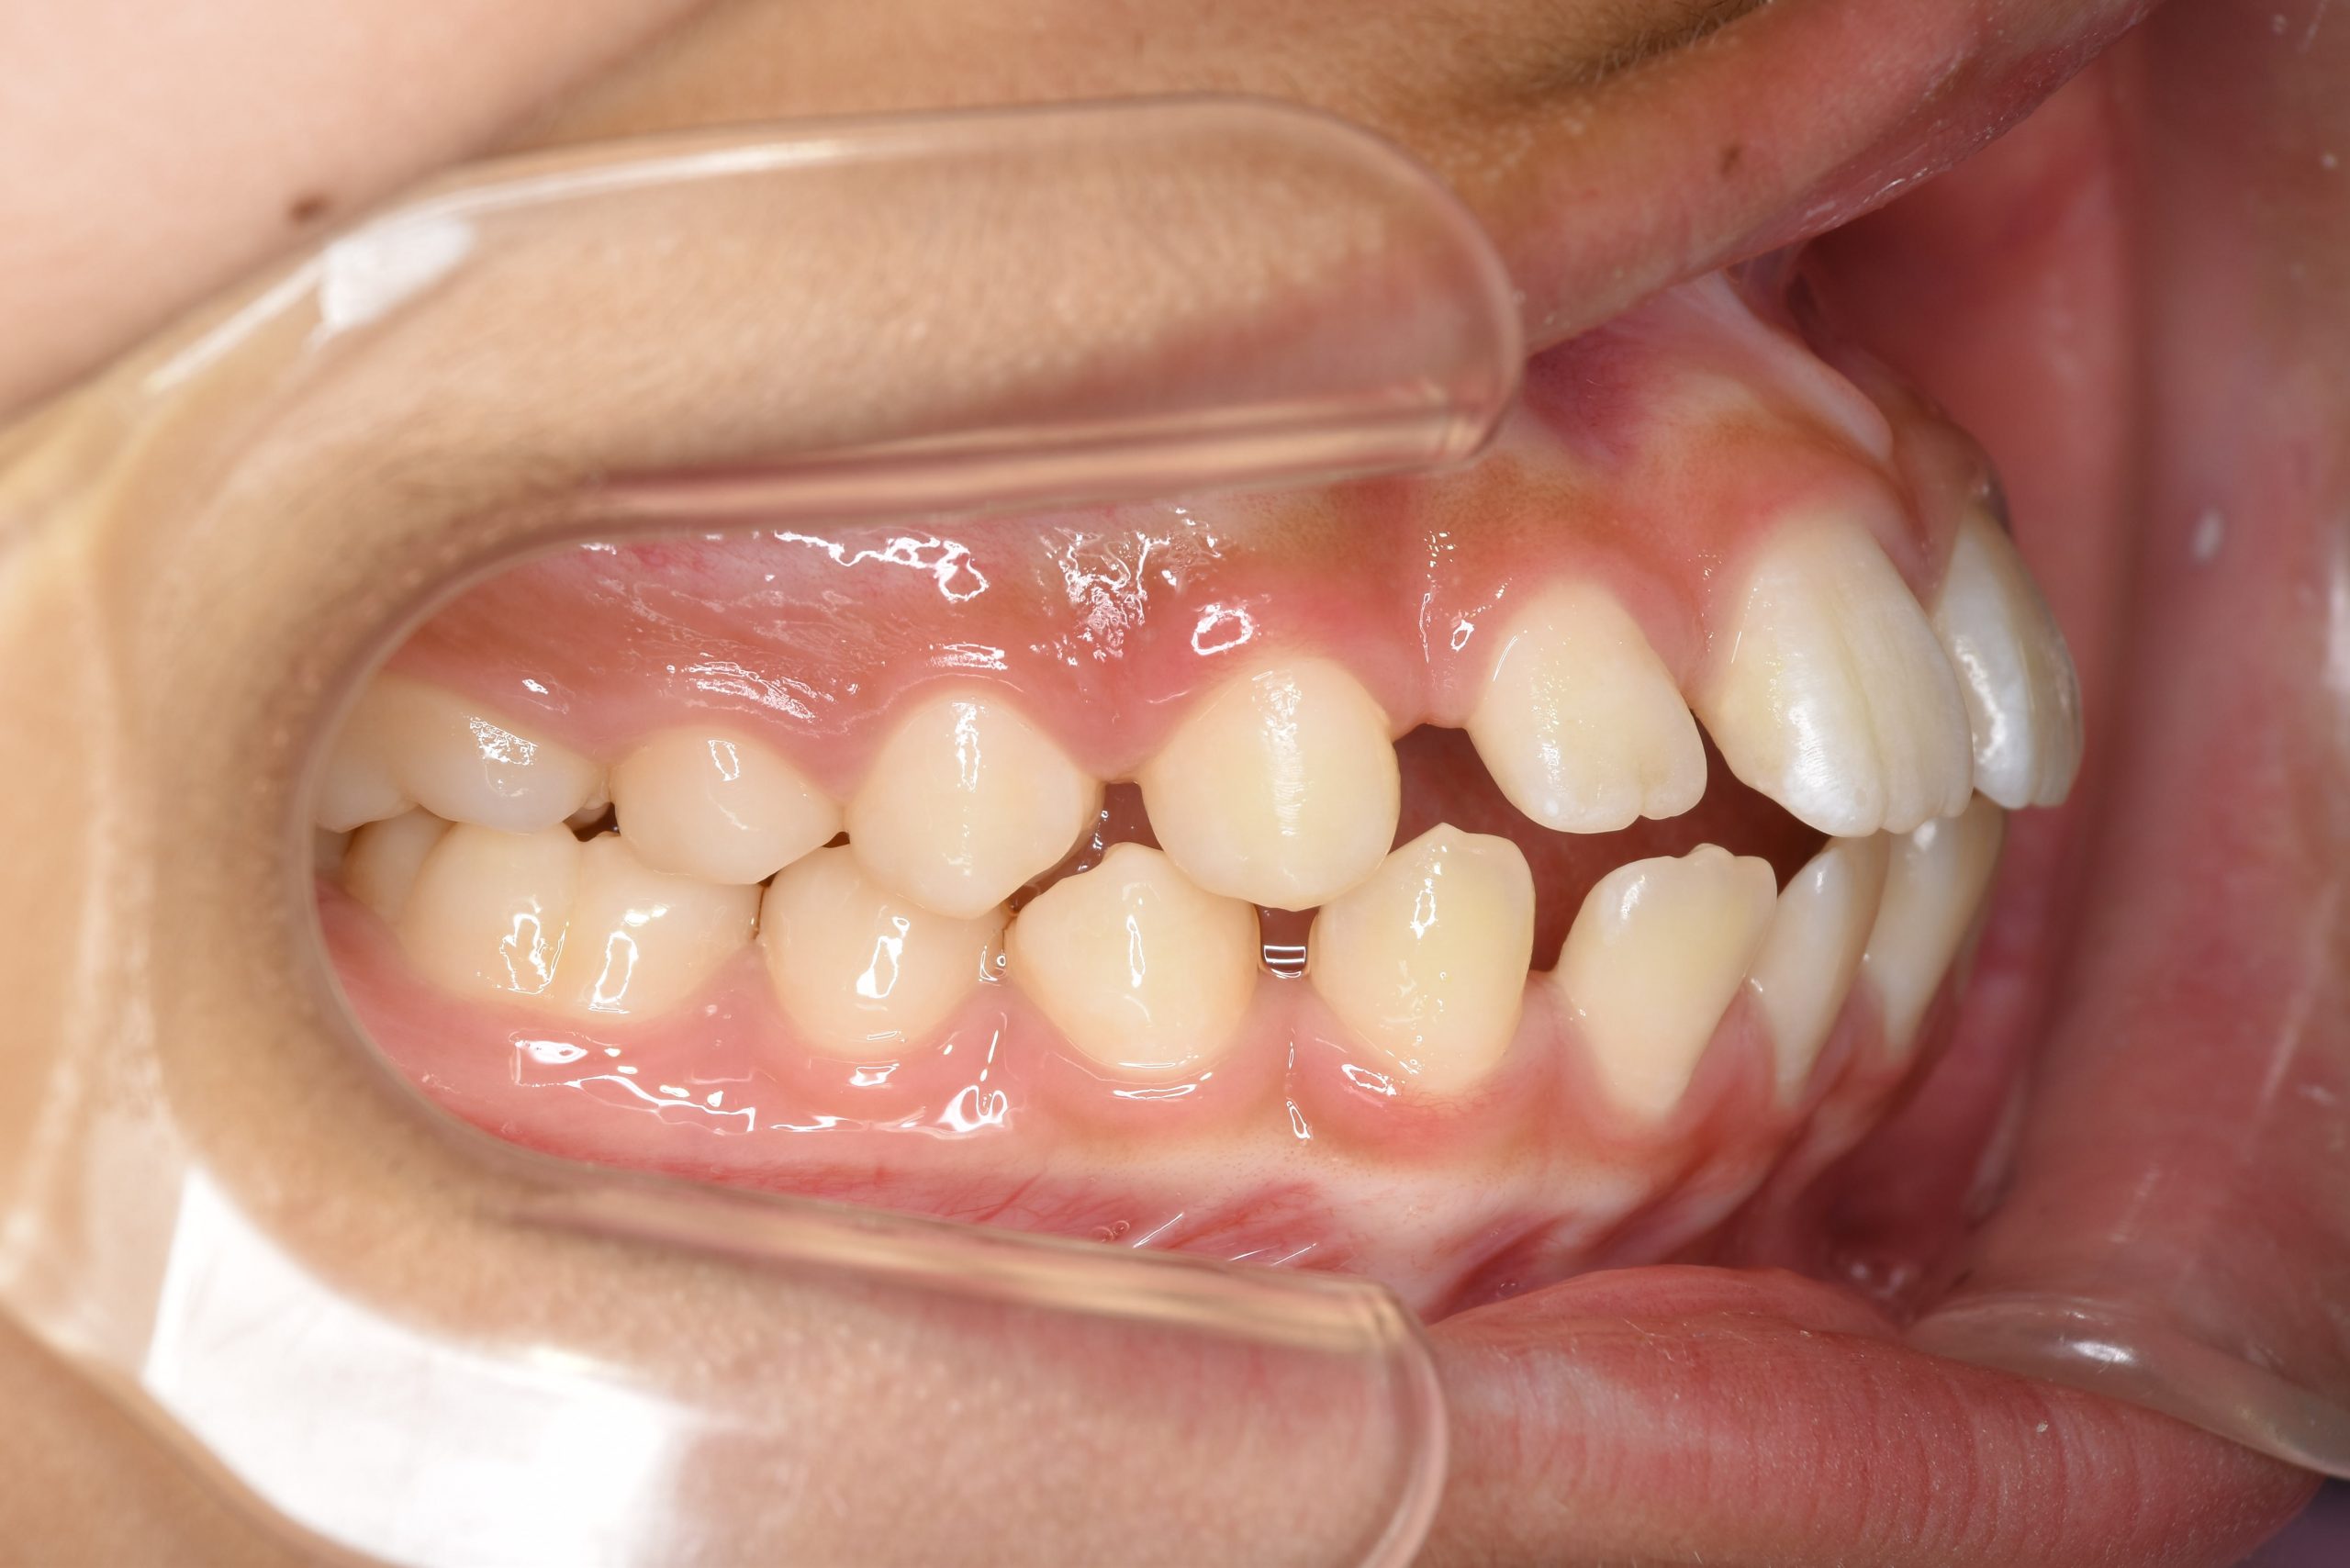

ビフォー

ワイヤー矯正治療|症例_681

主訴 上前歯が出ている|よく口が開いている

施術内容 上顎急速拡大装置と下顎リンガルアーチを用いて上下顎骨を拡大した。

その後マルチブラケット装置を用いて

非抜歯で歯牙を配列し良好な咬合を獲得した。

鼻閉症状は改善した。

治癒期間 2年10か月間